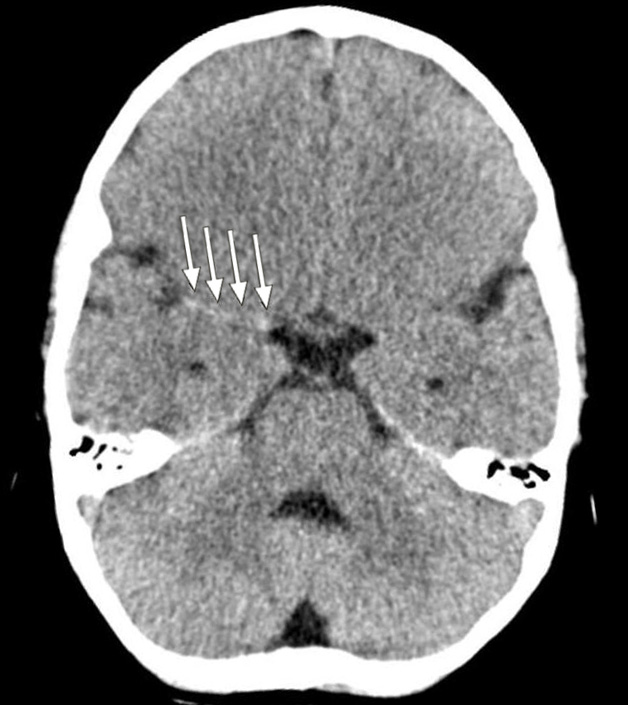

Et barn ble innlagt med en nyoppstått venstresidig hemiparese. CT caput ved innkomst viste «tett media-tegn» (dense media sign) (piler), noe som ga mistanke om en langstrakt trombe i høyre a. cerebri media (bildet til venstre). Pasienten fikk gradvis fallende bevissthetsnivå, og det ble gjort MR-undersøkelse. Denne viste nedsatt diffusjon som tegn på ferskt infarkt i hele forsyningsområdet til a. cerebri media samt begynnende ødem (bildet til høyre).